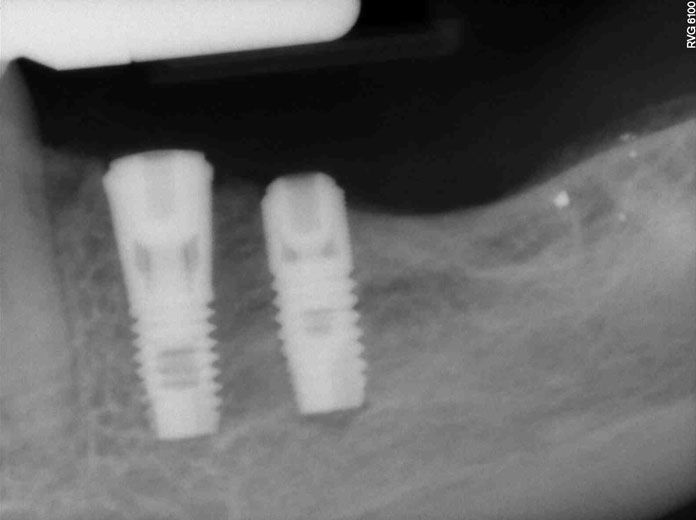

Αποκατάσταση έλλειψης ομάδος δοντιών

Όταν σε κάποια περιοχή του στόματος λείπουν τρία διπλανά δόντια, τότε τοποθετούμε δύο εμφυτεύματα και κατασκευάζουμε μεταξύ τους γέφυρα. Όσο αυξάνει ο αριθμός των ελλειπόντων δοντιών, τόσο μειώνεται η αντιστοιχία δοντιών-εμφυτευμάτων, π.χ. για την αντικατάσταση τεσσάρων ή και πέντε δοντιών συνήθως απαιτούνται τρία εμφυτεύματα.